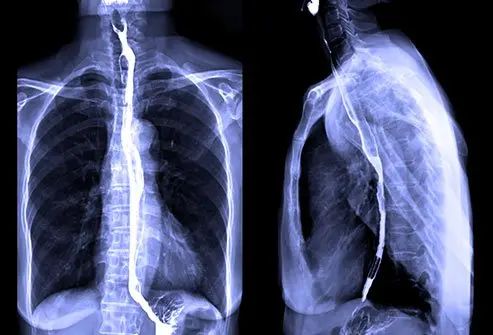

بیماریهای ریوی: مانند ذاتالریه، سل و تومورهای ریوی که با تصویربرداری قفسه سینه بهراحتی قابل شناسایی هستند.